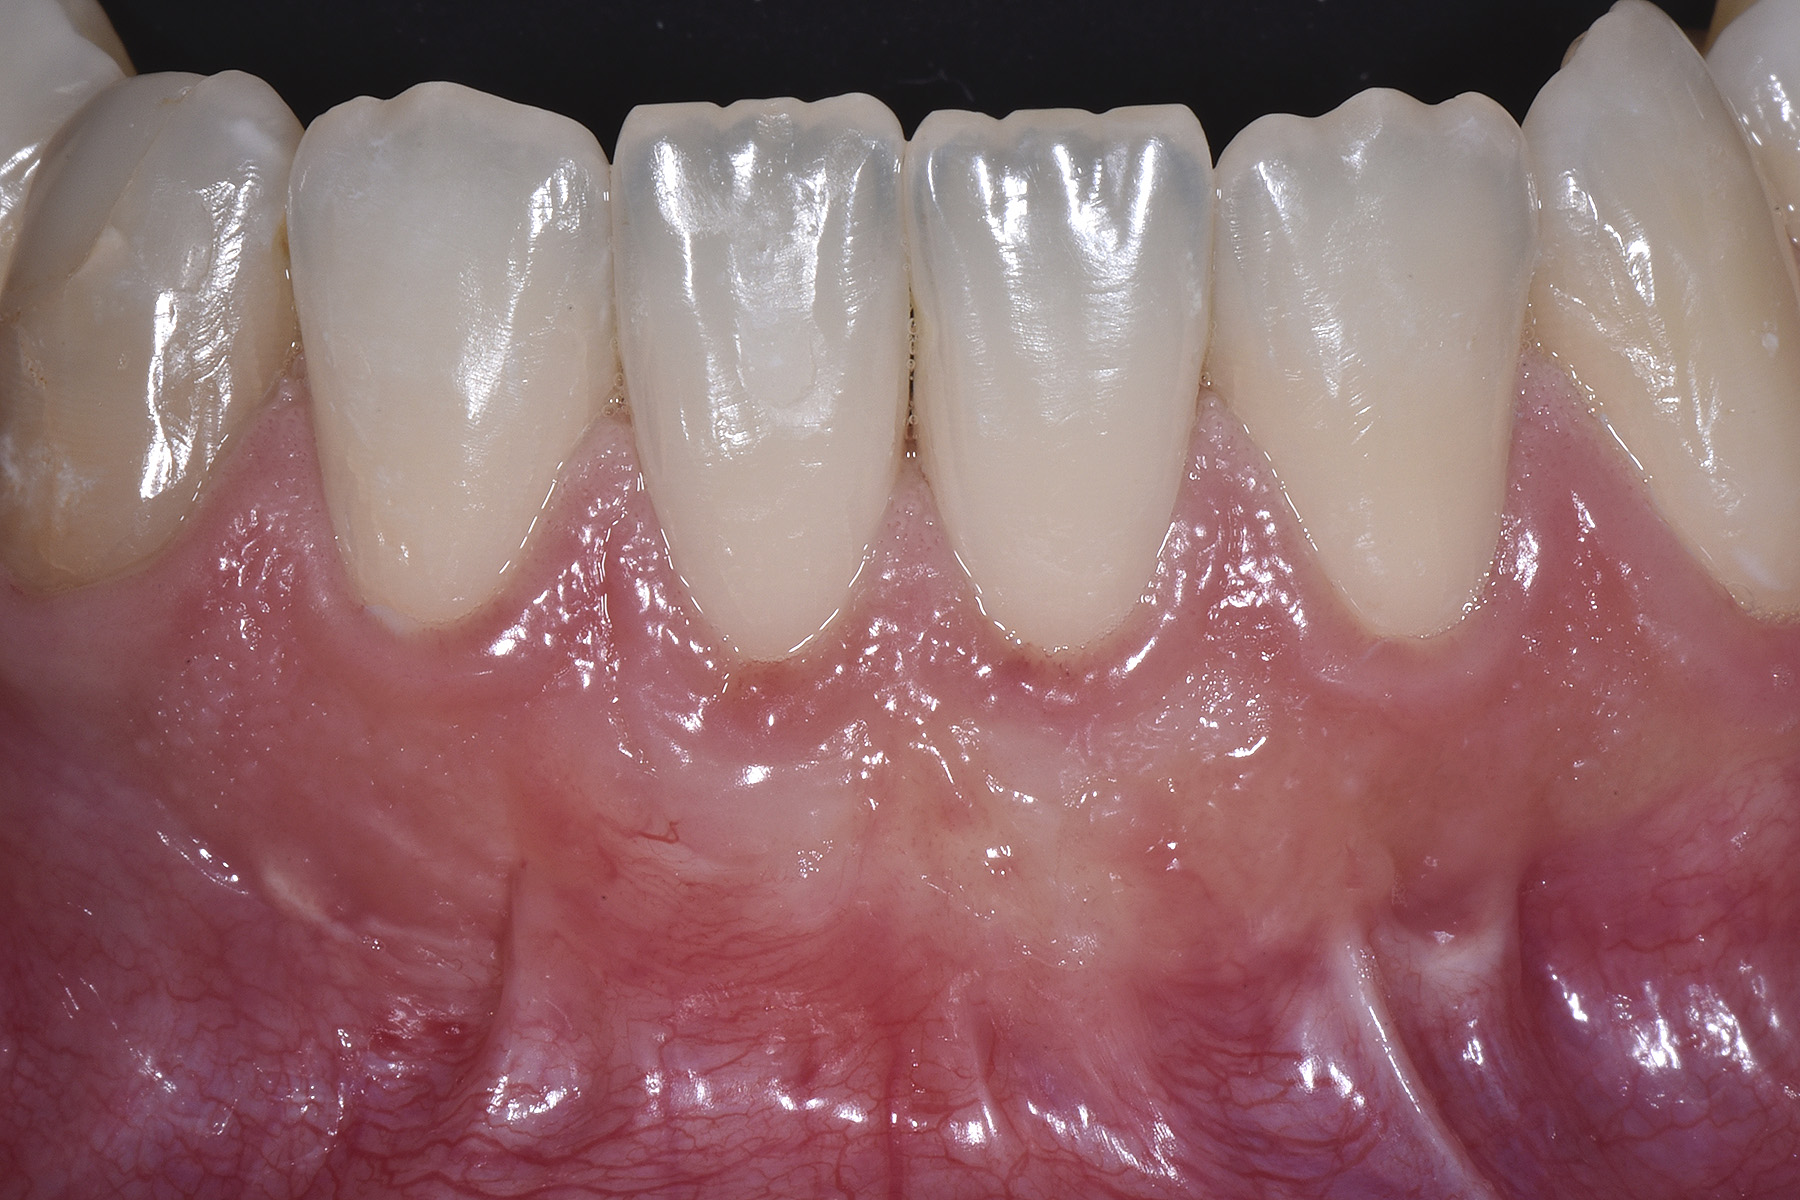

PREMESSA: in seguito all’estrazione dell’incisivo laterale superiore di destra, resasi necessaria per cause batteriche, si decide di affrontare il caso con il posizionamento di un impianto in sostituzione dell’elemento mancante dopo guarigione del sito infetto. Con tecniche rigenerative sia dei tessuti ossei mancanti a causa dell’infezione pregressa, sia dei tessuti gengivali che appaiono inizialmente troppo spostati in alto, si ripristina una corretta morfologia delle parabole (contorni) gengivali e delle papille interdentali (triangoli di gengiva tra due denti vicini).

Vengono utilizzati 2 tipi di provvisori: il primo, cementato ai denti vicini, viene utilizzato dal momento dell’estrazione del dente fino ad impianto osteointegrato (circa 6 mesi); il secondo, avvitato direttamente all’impianto, ha una funzione di prova estetica ma soprattutto di guida per la maturazione dei tessuti gengivali peri-implantari portandoli verso la maturazione completa prima di posizionare la corona finale in disilicato di litio.